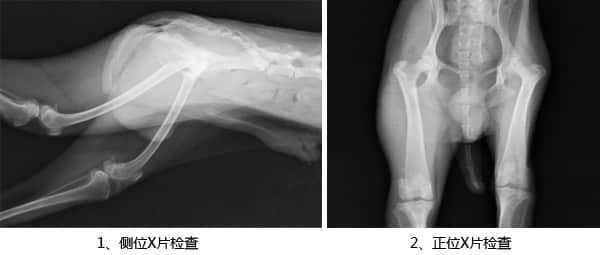

四、X线诊断

从图一可以看出该犬髌骨并没有异常,图二显示该犬股骨头有明显病变,股骨头完整性缺失,轮廓不清晰(箭头),患肢肌肉严重萎缩,患肢同侧髋臼密度增高。综合以上检查可以确诊该犬患有累-卡-佩氏病,即缺血性股骨头坏死,决定进行手术治疗。